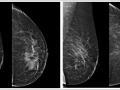

Achados mamográficos da resposta completa do câncer de mama à quimioterapia neoadjuvante.

Jan de 2021.

6.158

BI-RADS 6

clipe de titânio

linfonodo axilar

linfonodo axilar sus...

Mastologia